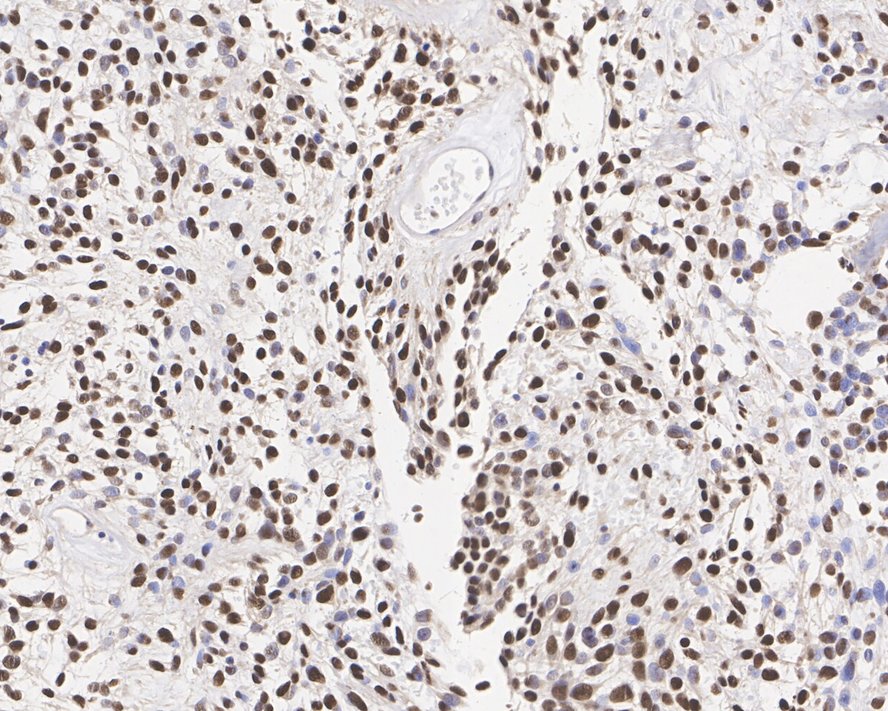

• Immunohistochemical analysis of paraffin-embedded human solitary fibrous tumor tissue with Rabbit anti-STAT6 antibody (<a href="/products/ET1605-49" style="font-weight: bold;text-decoration: underline;">ET1605-49</a>) at 1/1,000 dilution.<br /><br />The section was pre-treated using heat mediated antigen retrieval with sodium citrate buffer (pH 6.0) for 2 minutes. The tissues were blocked in 1% BSA for 20 minutes at room temperature, washed with ddH<sub>2</sub>O and PBS, and then probed with the primary antibody (<a href="/products/ET1605-49" style="font-weight: bold;text-decoration: underline;">ET1605-49</a>) at 1/1,000 dilution for 1 hour at room temperature. The detection was performed using an HRP conjugated compact polymer system. DAB was used as the chromogen. Tissues were counterstained with hematoxylin and mounted with DPX.

Immunohistochemical analysis of paraffin-embedded human solitary fibrous tumor tissue with Rabbit anti-STAT6 antibody (ET1605-49) at 1/1,000 dilution.

The section was pre-treated using heat mediated antigen retrieval with sodium citrate buffer (pH 6.0) for 2 minutes. The tissues were blocked in 1% BSA for 20 minutes at room temperature, washed with ddH2O and PBS, and then probed with the primary antibody (ET1605-49) at 1/1,000 dilution for 1 hour at room temperature. The detection was performed using an HRP conjugated compact polymer system. DAB was used as the chromogen. Tissues were counterstained with hematoxylin and mounted with DPX.